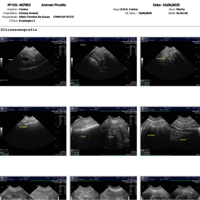

Comprovante do Ultrassom e do primeiro dia de tratamento para gastrite!

Comprovante do Ultrassom e do primeiro dia de tratamento para gastrite!

Comprovante do Ultrassom e do primeiro dia de tratamento para gastrite!

Comprovante do Ultrassom e do primeiro dia de tratamento para gastrite!